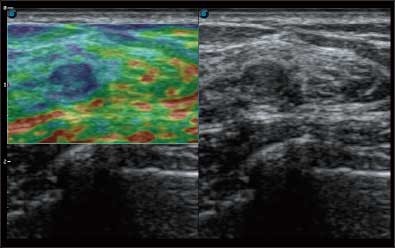

微米成像技术提升了对组织斑点噪声信号的抑制能力,并进一步强化边界信息,从而获得清晰图像。

通过对组织运动信息、血流信号及背景噪声进行准确智能的阈值判定,高效提取出微弱血流信号,获得高灵敏度和空间分辨率的血流图像,为临床提供更加真实和丰富的诊断信息。

全新算法处理射频信号 不可靠区域自动剔除 支持定量分析 压力曲线保证重复性